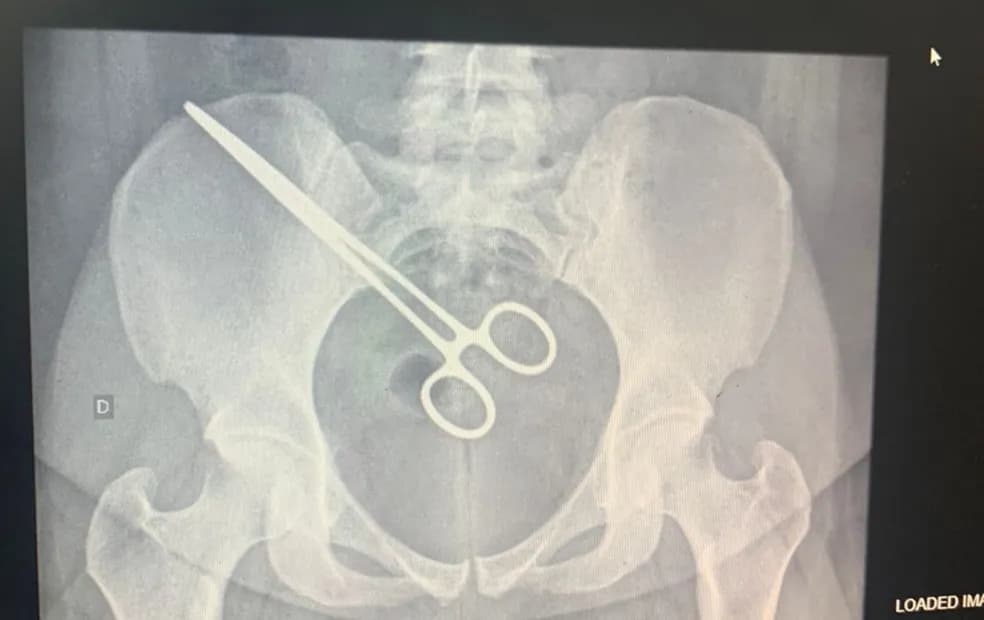

Idoso morre no Natal após ter pinça esquecida dentro do corpo, em MG

Mulher descobre pinça dentro do corpo ao visitar marido na cadeia em SP